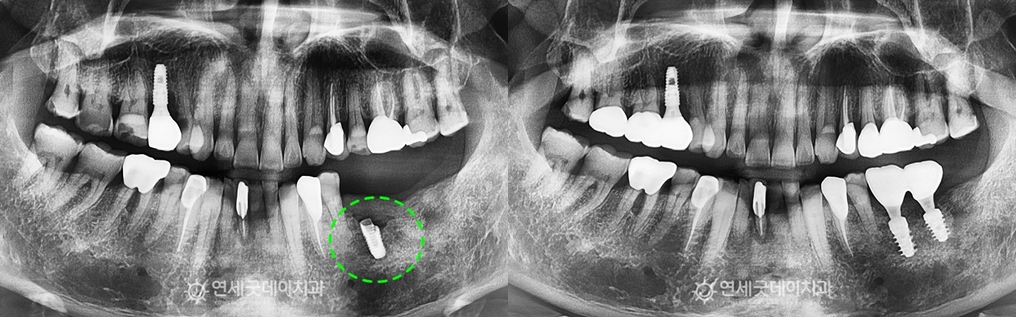

타원에서 치료 받으셨던 #36 부위의 픽스쳐 파절과

환자분은 저작력이 강하신 편으로 따라서 씹는 힘을 완화하고 치아를 보호하는 또한, 기존 픽스처를 제거한 후 임플란트 재수술과

결손 부위에는 스트라우만 BLX를 식립하였고

약 3개월 후, 잇몸뼈가 두툼하게 형성된 것이 확인되어 ‘스트라우만BLX’는 일반 티타늄 보다 1.8배 강한 #37 부위의 경우, 먼저 보철물을 올려도 되지만

타원 임플란트를 제거한 부위는 무엇보다 하치조신경관과 가까워 위험도가 긴 치료 받으시느라 고생 많으셨습니다. ^^ ※ 모든 사진은 본인의 동의를 얻어 동일조건에서 촬영하였으며 |